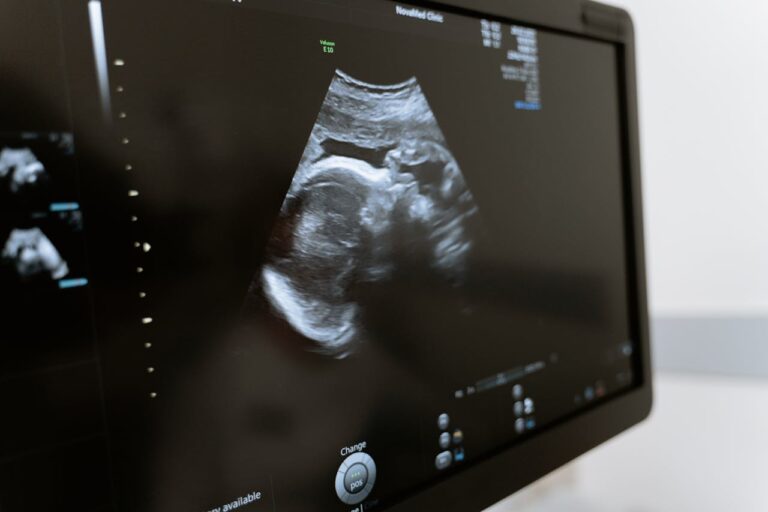

Experto en fertilidad explica: ¿En qué consiste la ovodonación y cuáles son los requisitos para realizar una?

En entrevista con CNN Chile, el doctor Pablo Hernández-Rudnick entregó detalles sobre este procedimiento del cual en Chile se han realizado cerca de mil ciclos.